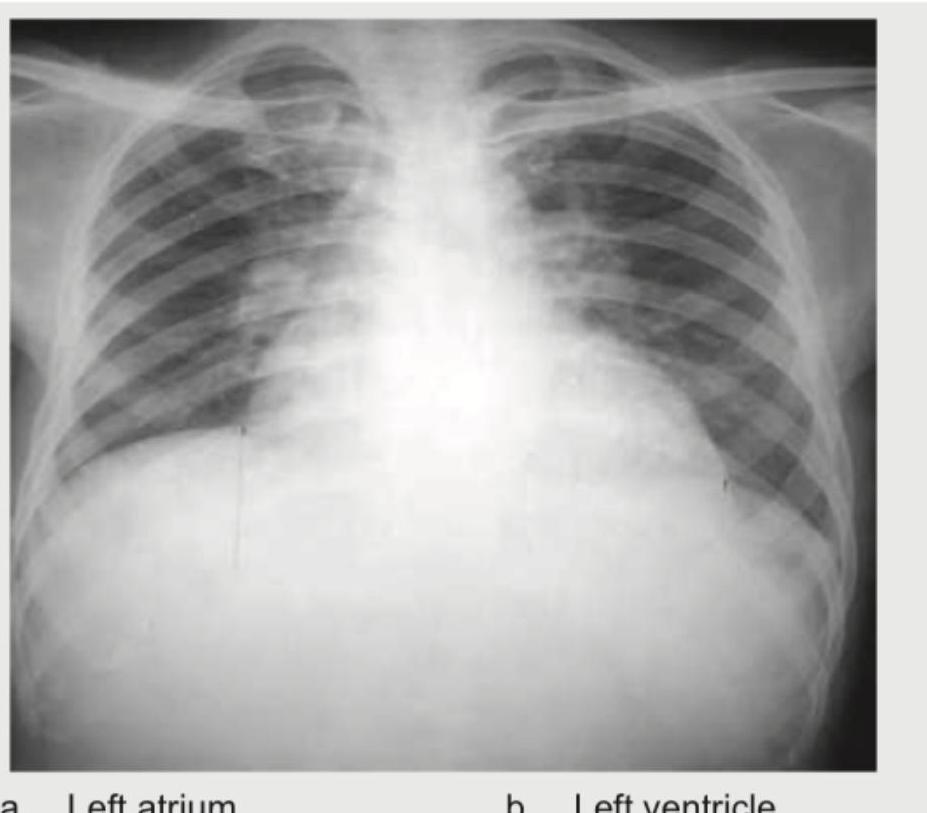

In the chest X-ray shown, identify the chamber enlargement:

Explanation: ***Left atrium*** - The chest X-ray shows **double contour sign**, an increased **carinal angle**, and **elevation of the left main bronchus**, all classic signs of **left atrial enlargement**. - The convexity of the left heart border appears straightened, and there might be a "bulge" or straightening of the **left cardiac border**, further indicating left atrial enlargement. *Right atrium* - Right atrial enlargement would typically show a prominent **convexity of the right cardiac border** extending further to the right. - This image does not demonstrate significant prominence or bulging of the right heart border beyond what is expected. *Left ventricle* - Left ventricular enlargement usually presents as increased **cardiac apex prominence** and **downward displacement** of the cardiac apex. - While there is some cardiomegaly, the primary signs visible (double contour, carinal angle change) point more specifically to left atrial enlargement. *Right ventricle* - Right ventricular enlargement typically manifests as **increased prominence of the right ventricle** along the left heart border and an **uplifted cardiac apex**. - No clear evidence of right ventricular specific enlargement signs like severe right heart border prominence or uplifted apex is seen here.